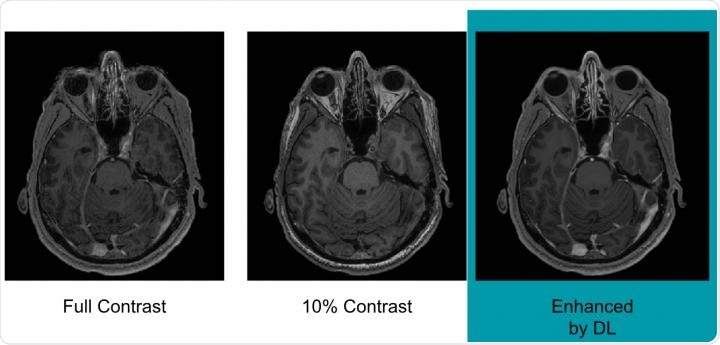

Example of full-dose, 10 percent low-dose and algorithm-enhanced low-dose - Radiological Society of North AmericaExample of full-dose, 10 percent low-dose and algorithm-enhanced low-dose. Credit: Radiological Society of North America.

Pre-contrast scans carried out before any contrast had been administered were referred to as zero-dose scans; those that used 10% of the standard gadolinium dose were referred to as low-dose scans and those that used 100% of the standard dose were referred to as full-dose scans.

The results showed that the image quality did not differ significantly between the three scan sets and also indicated that the equivalent of full-dose scans could be generated without using any gadolinium at all.